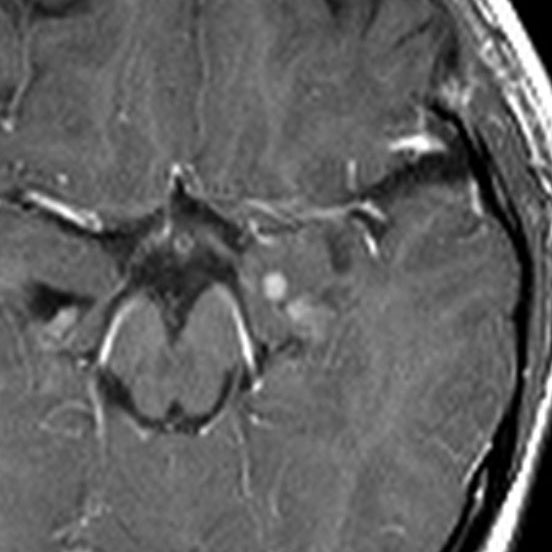

左内側側頭葉グリオーマ mesial temporal glioma と呼ばれる腫瘍です。左の扁桃体,海馬鉤,海馬,海馬傍回に腫瘍が浸潤しています。T2強調画像とFLAIRでまだらな高信号で境界ははっきりしません。mass effectが少なく,増殖増大傾向のある腫瘍には見えないのが特徴です。下段右のように部分的にガドリニウム増強されるのも神経節細胞腫の特徴かもしれません。しかし,神経節膠腫,乏突起膠腫,乏突起星細胞腫(グレード2)なども疑われます。

手術中の脳波モニターでは,棘波が上側頭回の後方(ウェルニッケ領域)に存在し,深部電極刺入で海馬近傍にも棘波がみられましたが,もちろん上側頭回や海馬の切除はしませんでした。扁桃体 amygdala と海馬鈎 uncus の腫瘍部分のみを切除して手術を終了しています。海馬と海馬傍回には腫瘍を残しました。上のMRIは,その後6年経過した後のものですが腫瘍は全く同じ大きさです。抗てんかん薬も止めて,発作は全く生じていません。このような腫瘍は,扁桃体と海馬鉤を摘出することで,発作を完全に止めることができることがあります。ですから,最初の手術では,リスクのある余分な脳切除をしません。